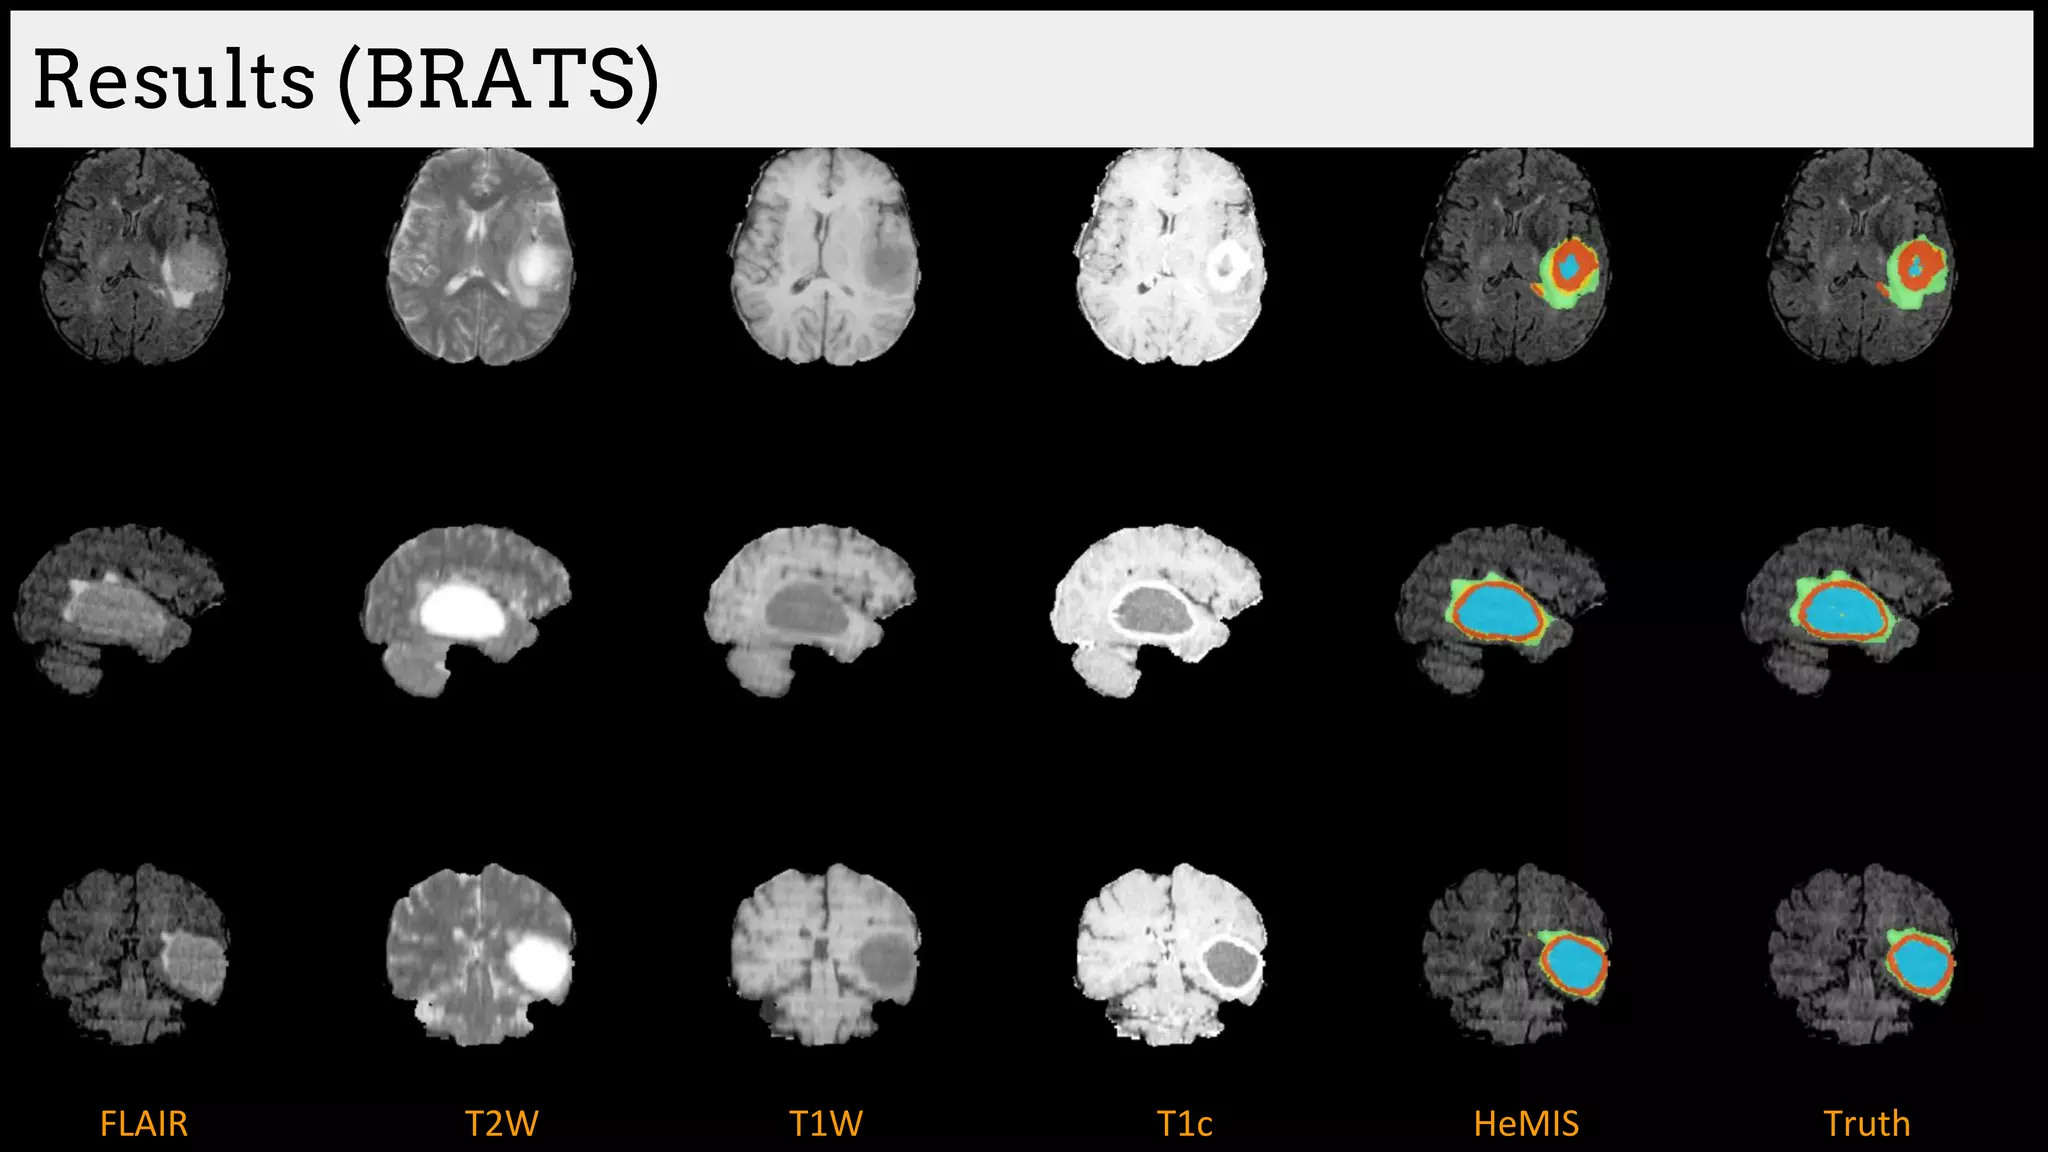

Results (BRATS)

Brain tumor segmentation (BRATS2013 dataset)

T1 T2

T1C Flair

GT

Edema

Necrosis

Non-enhanced

Enhanced

Training data:

220 subjects with high grade and

54 subjects with low grade tumors

Dice Similarity

[Havaei et al. HeMIS: Hetero-Modal Image Segmentation, MICCAI 2016]